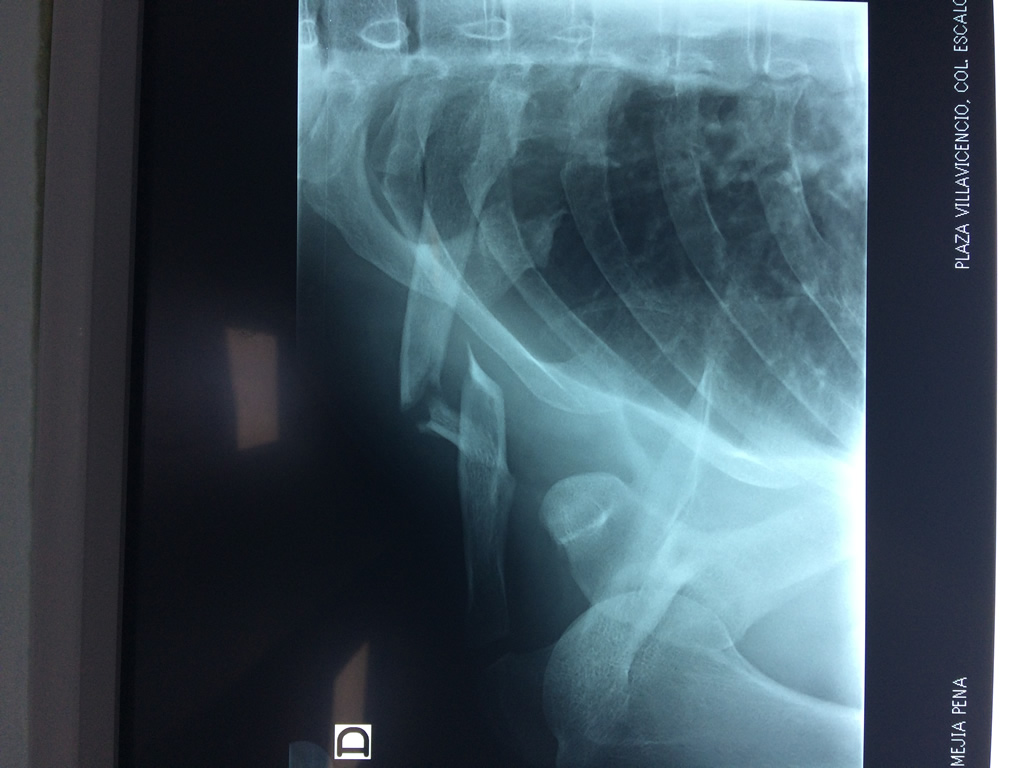

Cirugías de Codo - Clavícula

La clavícula es un hueso largo, con forma de "S" itálica, situado en la parte anterosuperior del tórax. Junto con la escápula forman la cintura escapular. Se puede palpar por toda su longitud y se extiende del esternón al acromion de la escápula, siguiendo una dirección oblicua lateral y posterior.